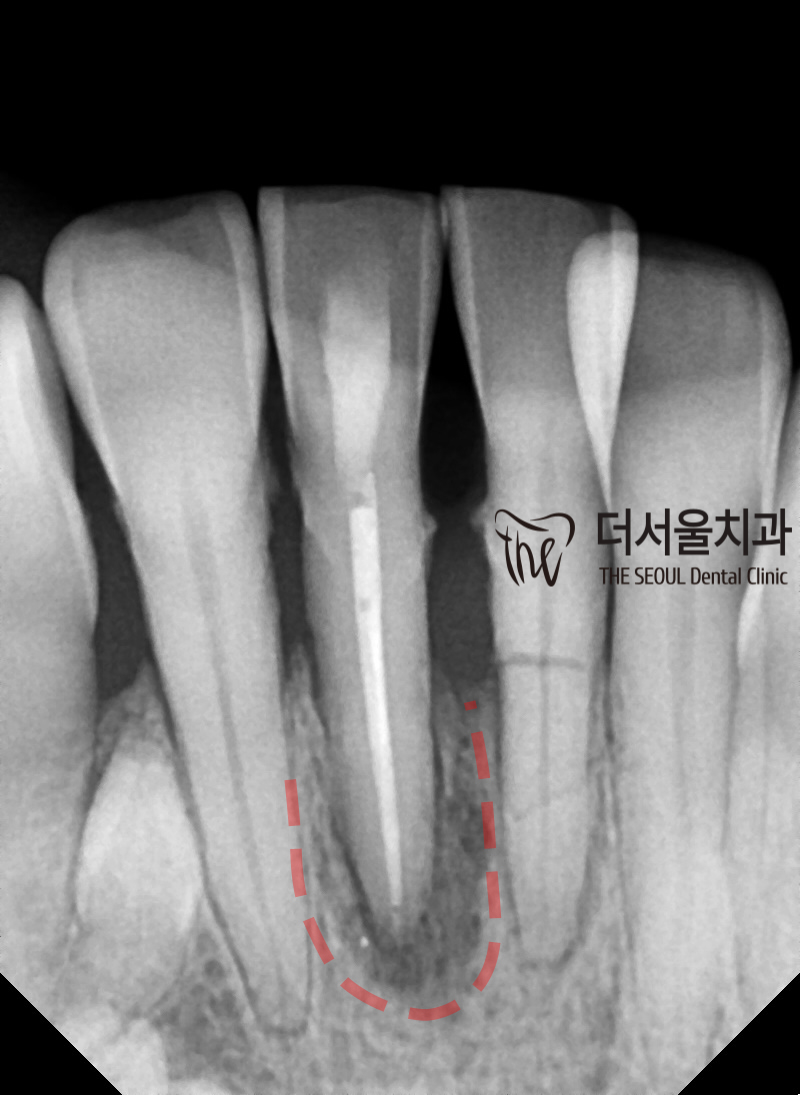

촬영을 통해 살펴보니

이전에 신경치료를 받았던 곳에

재감염이 일어나 치근단염증 이 생겨있었습니다.

표시해둔 곳을 보면

치아 뿌리 주변으로 검게 퍼져 있는

병소의 흔적을 살펴볼 수 있었는데요.

아무래도 이곳이 흔들림의 원인이 아닐까..

짐작이 되는 상황이네요.